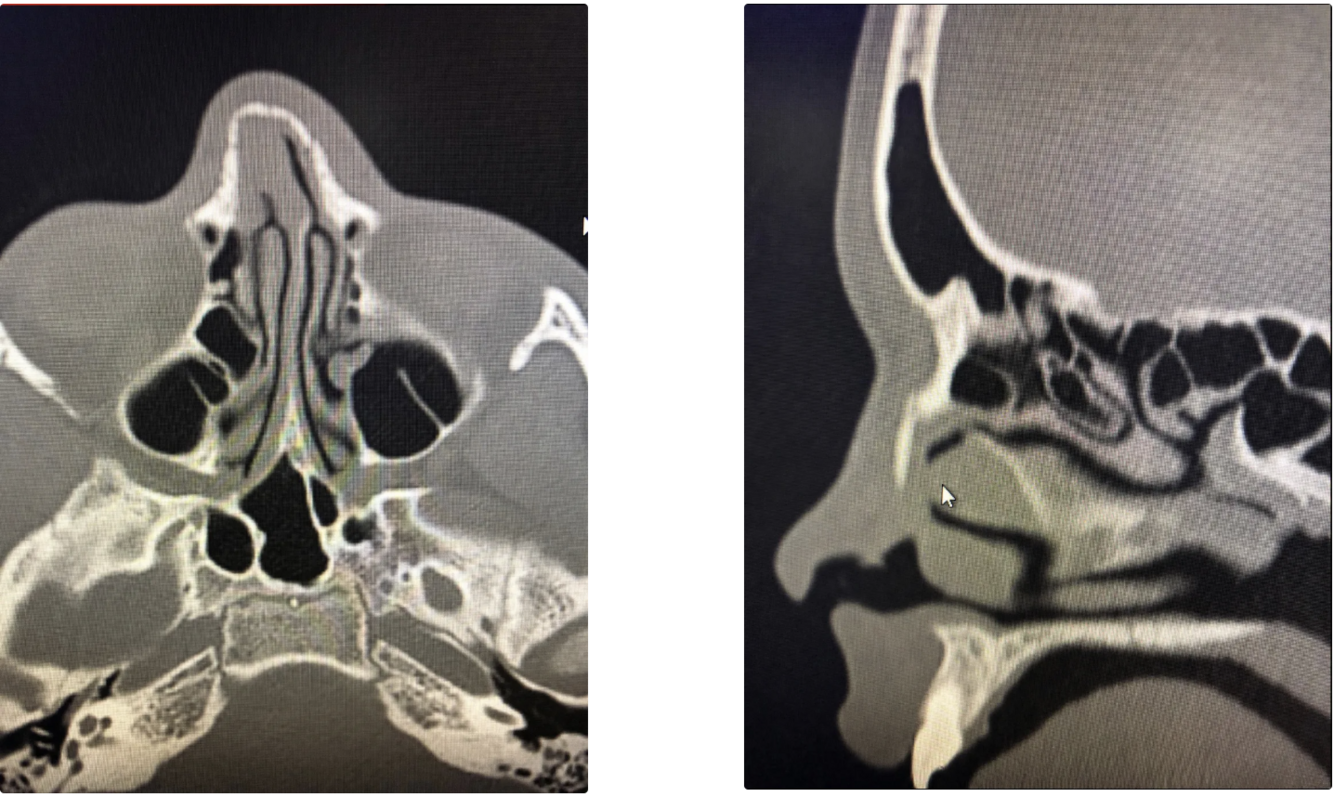

TAC nasal típica de fractura (axial/coronal/sagital): ¿Qué hallas?

A

• Líneas hipodensas de fractura

• Desplazamiento de HPN

• Conminución si es severa; a veces hematoma septal o engrosamiento mucoso